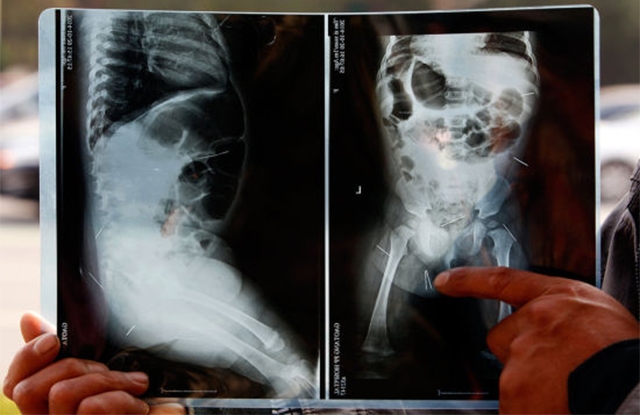

Sau khi chụp X-quang, các bác sĩ đã phát hiện 12 cây kim trong cơ thể một bé gái ở Trung Quốc.

Tin tức trên Sina cho biết, tại một bệnh viện ở Liêu Thành, tỉnh Sơn Đông (Trung Quốc), bố mẹ của bé gái 11 tháng tuổi Fan Zizuan kinh ngạc khi biết trong cơ thể con gái có tới 12 cây kim bằng thép, sau khi xem hình ảnh chụp X-quang ngày 20/10.

Hình ảnh X-quang cho thấy, 12 cây kim trong cơ thể bé gái 11 tháng tuổi.

Sau đó, vợ chồng Liu đã rất ngạc nhiên khi nhìn thấy ảnh chụp X-quang cơ thể con gái của họ. Ảnh X-quang cho thấy, 12 chiếc kim trong bụng và mông của bé Fan.